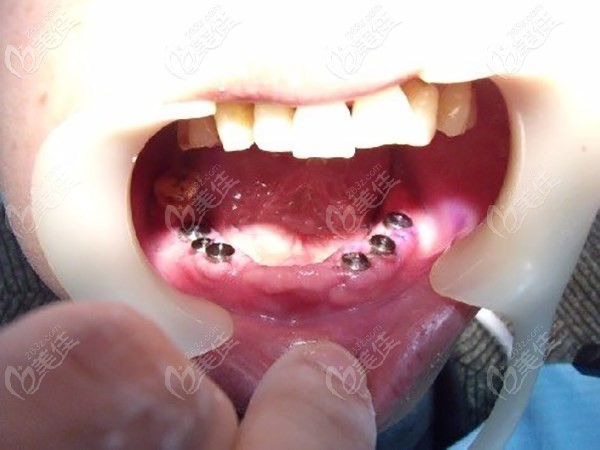

術前照片:

牙齒癥狀:70歲的李大爺,上牙松動,下牙壞死并缺失多顆,殘存的牙齒大多也松動了。

這位70歲的老人來院,初步面診時候,牙齒問題已經相當嚴峻了,下牙缺失很多,上牙松動也很明顯。

從上圖可以看出老人下牙壞死并缺失多顆,殘存的也都松動了,根據老人牙槽骨條件,醫(yī)生給老人的建議是做半口種植牙修復,這個技術院內做的比較成熟,成功率也比較高,老人可能對這個也不了解,說是要考慮考慮。